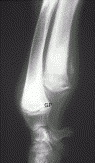

• Osteochondrosis

Elbow

• Elbow dysplasia

• Osteochondrosis of the medial humeral condyle

• Tarsal osteochondrosis(itis) dissecans